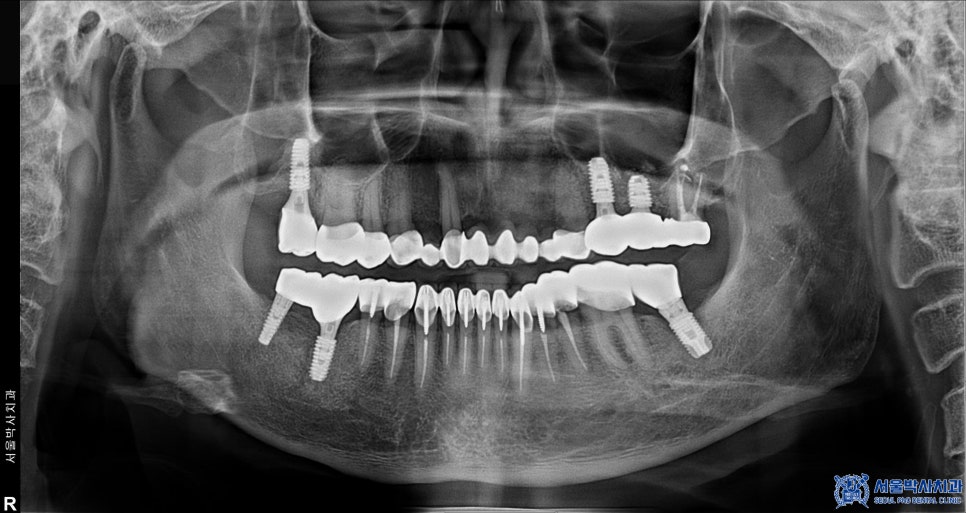

재수술에 만족하신 환자분께서는

추가적으로 위쪽 어금니에도

임플란트 식립을 진행하셨습니다.

또한 위쪽 어금니 중 일부는

신경치료 후 크라운 치료로 충분히 유지할 수 있는

상태였기 때문에 발치를 진행하지 않고

기존 보철물을 제거한 후,

신경치료를 진행하여 새롭게

보철 치료를 시행하였습니다.

이처럼 서울박사치과에서는

자연치아를 살릴 수 있다면

보존하는 방향으로 치료를 진행합니다.